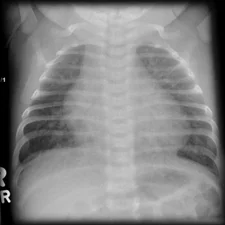

The pulmonary vascular pattern refers to the arrangement and structure of blood vessels in the lungs, important for diagnosing various respiratory and cardiovascular conditions.